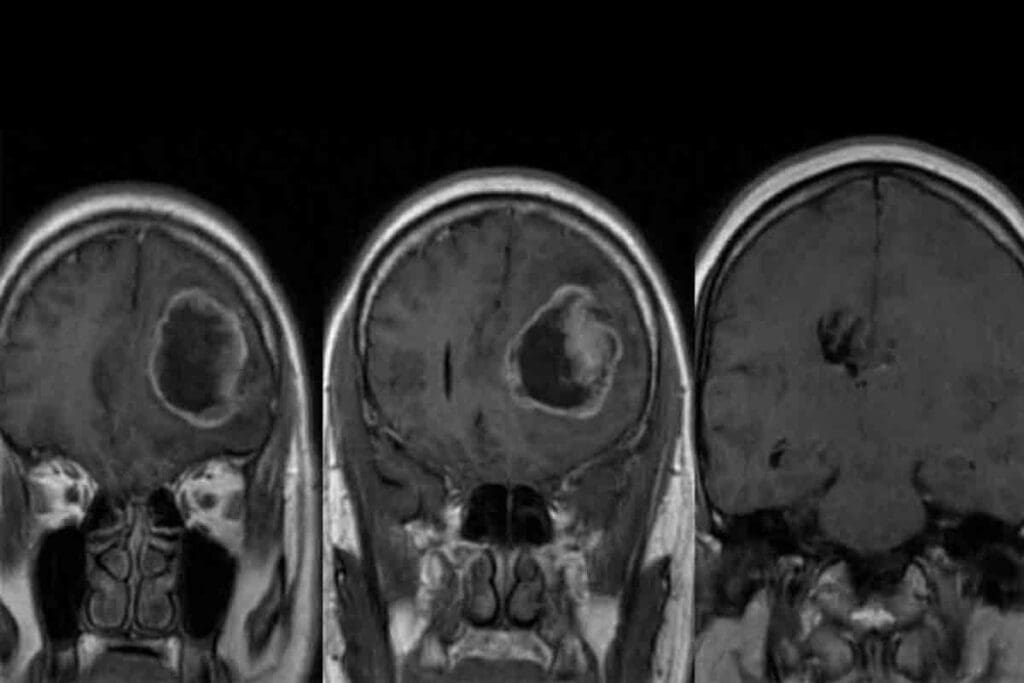

Imaging Studies (MRI, CT Scans)

Imaging is vital for diagnosing pediatric GBM. MRI and CT scans help us see the tumor in the brain. MRI gives us clear images of soft tissues, showing the tumor’s size and where it is.

Surgical Approaches

Surgery is often the first step in treating pediatric GBM. The goal is to remove as much of the tumor as possible. This is done carefully to avoid harming the brain.

The surgery method depends on the tumor’s location and size. Modern tools like intraoperative MRI help surgeons remove the tumor more accurately.